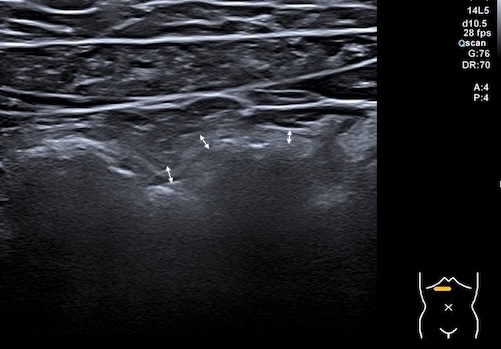

Sigmoïde basse fréquence

Même lésions avec la sonde haute fréquence, épasissement de 7 mm prédominant à la 3 ième couche, c'est à dire la sous muqueuse, hyperéchogène

Ici score de Milan = (1,4 x7+2)=11,8 maladie très active.